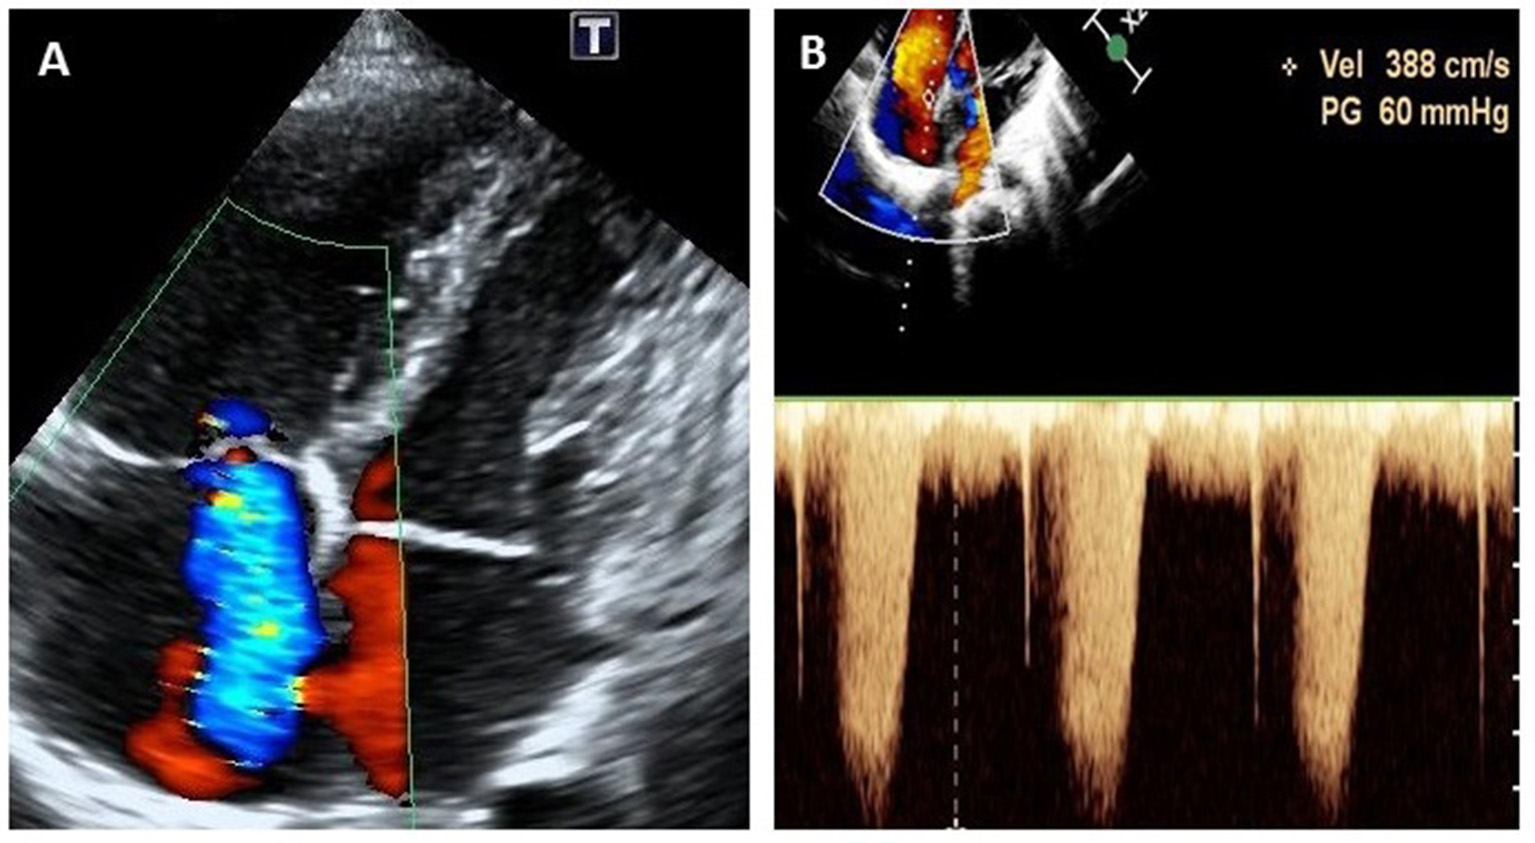

One year later, at the age of 9 years, the child was again brought to the hospital with complaints of edema and easy fatiguability on ambulation. On physical examination, significant findings including systemic edema, hepatomegaly, and a pronounced second heart sound. Laboratory results showed elevated levels of both erythrocyte sedimentation rate (70 mm/h; normal reference range: 0–30 mm/h) and N-terminal pro b-type natriuretic peptide (NT-proBNP) (1,381 pg/ml; normal reference range: 0–84 pg/ml). On echocardiography, the estimated systolic pulmonary arterial pressure (PAP; evaluated on the basis of the tricuspid regurgitation velocity), was 60 mmHg, suggestive of PAH (Figure 2). Bilateral coronary aneurysms were also detected. A general CT scan of the aorta revealed dilatation of the aortic sinus. The bilateral pulmonary and coronary arteries were also found to be dilated (Figure 3), while the abdominal aortic stem and the distal section of the superior mesenteric artery showed minor dilatation. An electrocardiogram revealed ST-segment and T-wave changes. There were no other findings suggestive of connective tissue disease, and a contrast-enhanced abdominal CT scan did not show the presence of an intrahepatic shunt. The child's family refused a right heart catheterization procedure. Therefore, the patient was diagnosed with (1) CAEBV; (2) PAH; (3) cardiac insufficiency (Class III); and (4) systemic vasculitis and managed conservatively. He was administered immunosuppressants (prednisolone 25 mg qd), the targeted pulmonary pressure-reducing drugs (sildenafil 25 mg bid and bosentan 31.25 mg bid) and antiplatelet therapy (clopidogrel 50 mg qd). The patient was also administered cyclophosphamide 4 times pulse therapy once every 2 weeks, with a cumulative 4-g dose of the drug. This combination therapy resulted in a decrease in his systolic PAP to 40 mmHg on echocardiography, and a reduction of NT-proBNP level to 62.3 pg/ml.

FIGURE 2

www.frontiersin.org

Figure 2. Echocardiogram (apical four-chamber view) at the onset of pulmonary arterial hypertension at 9 years of age, showing severe tricuspid regurgitation (A) and continuous wave doppler estimation of tricuspid reflux velocity 3.88 m/s, PG = 60 mmHg (B).